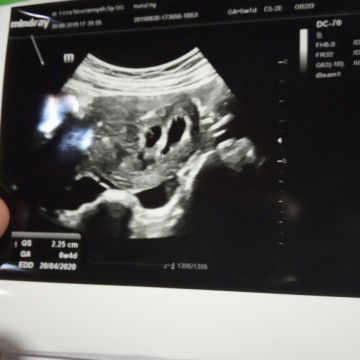

perkiraan kembar

Bund, usia kandunganku 6 week, kemarin pas usg dokter bilang perkiraan punya calon ddek kembar.. Apa benar ya bund?? Kan usia kandungannya baru segitu kok udah bisa di prediksi gitu ya.. Sharing dong bund, ada yang pernah kayak gitu gak??